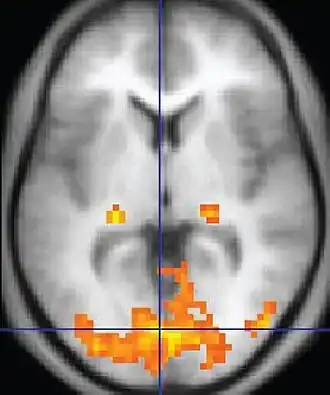

Functional MRI (fMRI) Blood-oxygen-level dependent imaging BOLD Changes in oxygen saturation-dependent magnetism of hemoglobin reflects tissue activity.[92] Localizing brain activity from performing an assigned task (e.g. talking, moving fingers) before surgery, also used in research of cognition.[93]